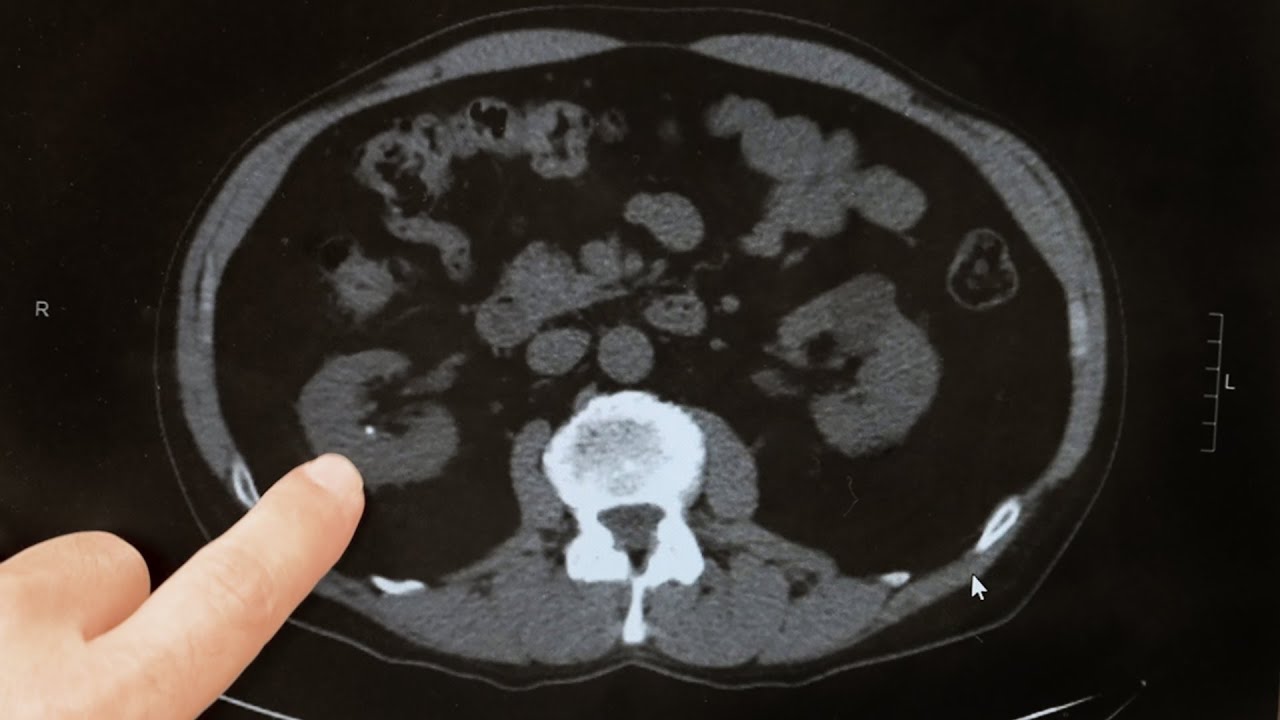

Kidney stones are made up of millions of tiny crystals that form when there is an imbalance in water, minerals and salts. Most kidney stones form on the interior surface of the kidney where urine leaves the kidney tissue and enters the urinary collecting system. Kidney stones can be small like a grain of sand but are often much larger.

Most people are diagnosed with kidney stones due to pain which can sometimes be excruciating though it will often wax and wane while others may have more mild pain. Severe pain typically occurs when the kidney stone breaks loose and falls into the ureter, the tube that runs from the kidney to the bladder. Stones can block the drainage of urine from the kidney, a condition known as renal colic. The pain may begin in the lower back and may move to the side or even to the groin. Other symptoms may include blood in the urine (hematuria), frequent or persistent urinary tract infections, urinary urgency or frequency and nausea or vomiting.

Small kidney stones (less than 5 mm) not causing any pain are often observed as there is a good chance these stones will pass spontaneously when they fall] into the ureter. However, there are a number of reasons to treat a kidney stone even if it is not causing pain. Some kidney stones may be infected, and in many cases, despite proper antibiotic treatment, the infection cannot be cleared from the stone. In such cases, the only way to eradicate the infection completely is to remove the stone. Staghorn stones are extremely large stones that grow to fill the inside of the kidney. There are serious health risks associated with these stones and left untreated they are associated with an increased risk of kidney failure. There are also additional situations in which even small stones should be treated. For example, the Federal Aviation Administration (FAA) will not allow a pilot to fly until all stones have been cleared from his or her kidney. A few other occupations also do not allow for the unplanned passage of a kidney stone. Likewise, frequent travelers, whether for business or otherwise, especially to places where medical care is not reliable, should consider treatment. Others may choose to remove their stones at a time when it is convenient for them in order to avoid the unpredictable future passage.

PCNL is a technique used to remove certain stones in the kidney or upper ureter (the tube that drains urine from the kidney to the bladder) that are too large for other forms of stone treatment such as shock wave lithotripsy or ureteroscopy.

This procedure is accepted as the standard of care for patients with kidney stones that are large, very firm, or resistant to other forms of stone treatment. It has replaced open operations for kidney stones in the vast majority of patients. Typically, the length of the surgery is three to four hours. The surgery is performed by making a small 1 cm incision in the patient’s flank area. A tube is placed through the incision into the kidney under x-ray guidance. A small telescope is then passed through the tube in order to visualize the stone, break it up and remove it from the body. If necessary a laser or other device called a lithotripter may be used to break up the stone before it can be removed. This procedure has resulted in significantly less post-operative pain, a shorter hospital stay, and earlier return to work and daily activities when compared to open stone surgery.